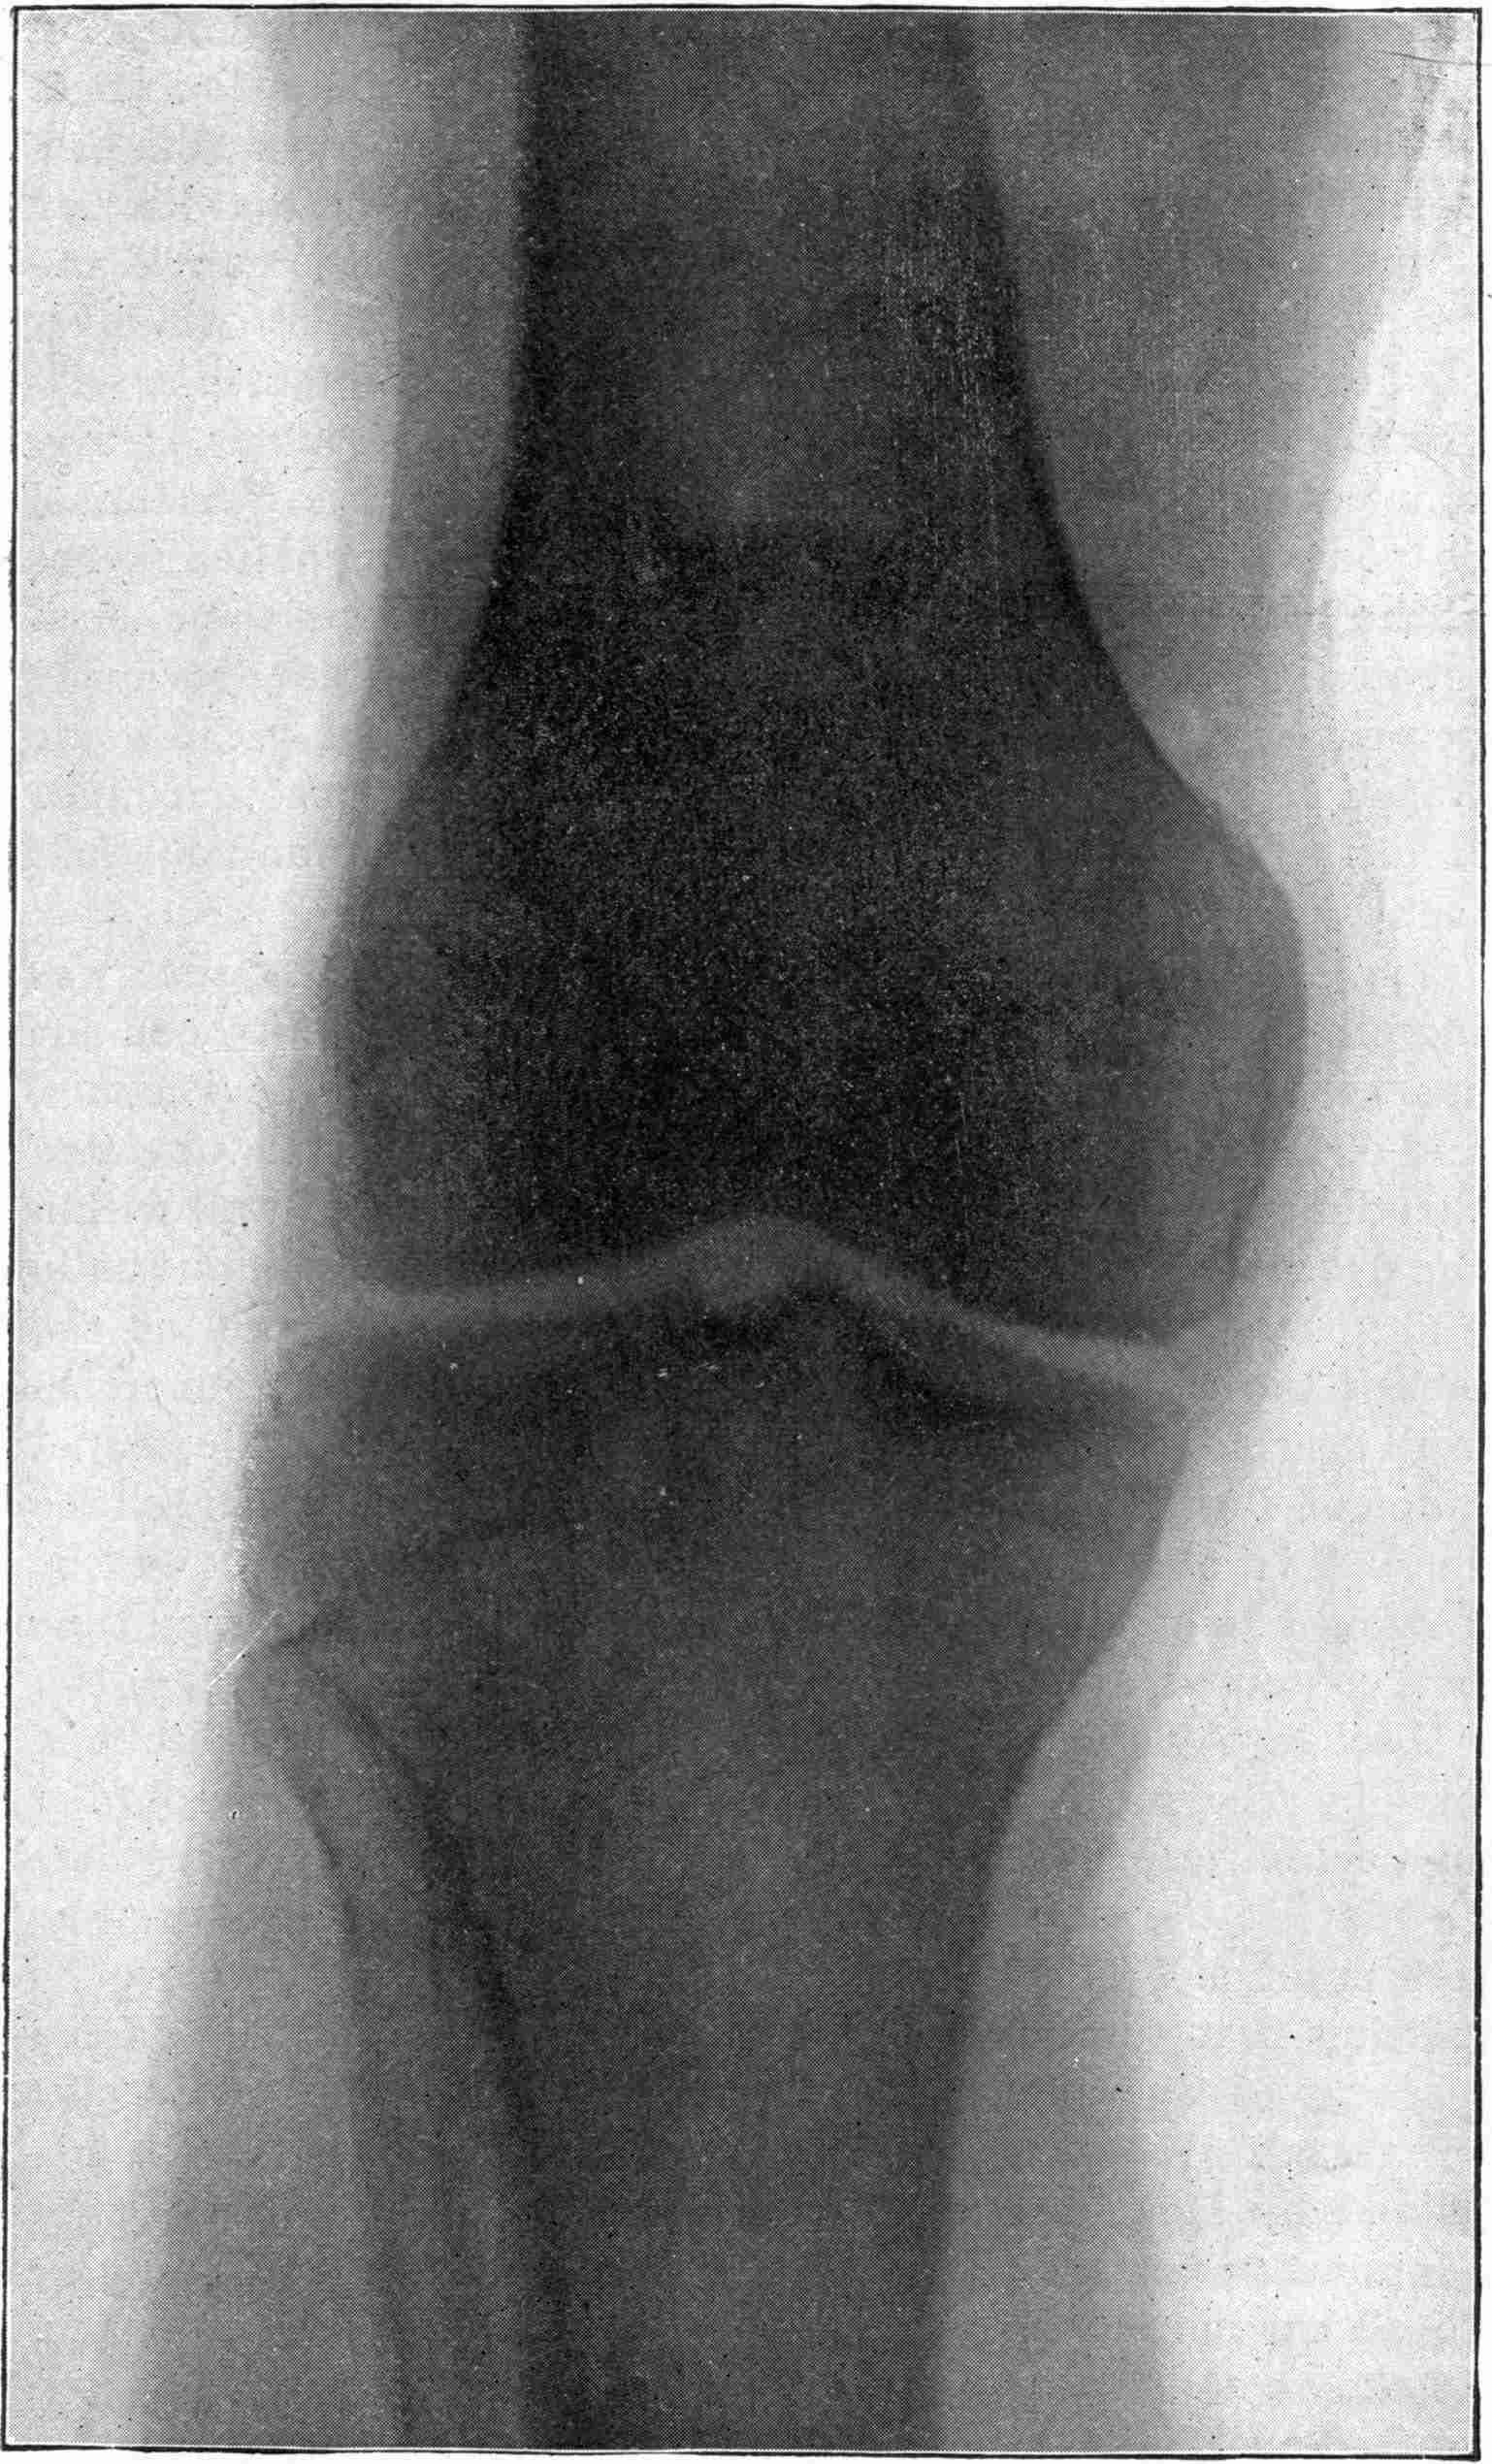

Fig. 4.—Knee, Knickerbocker Buttons, Bullet in Femur.